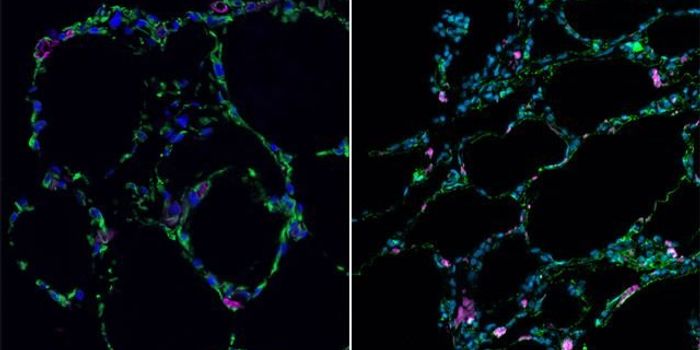

OCT 21, 2024CancerLung cancer remains a severe malignancy, expected to account for over 125,000 deaths in 2024. With high rates of m ...